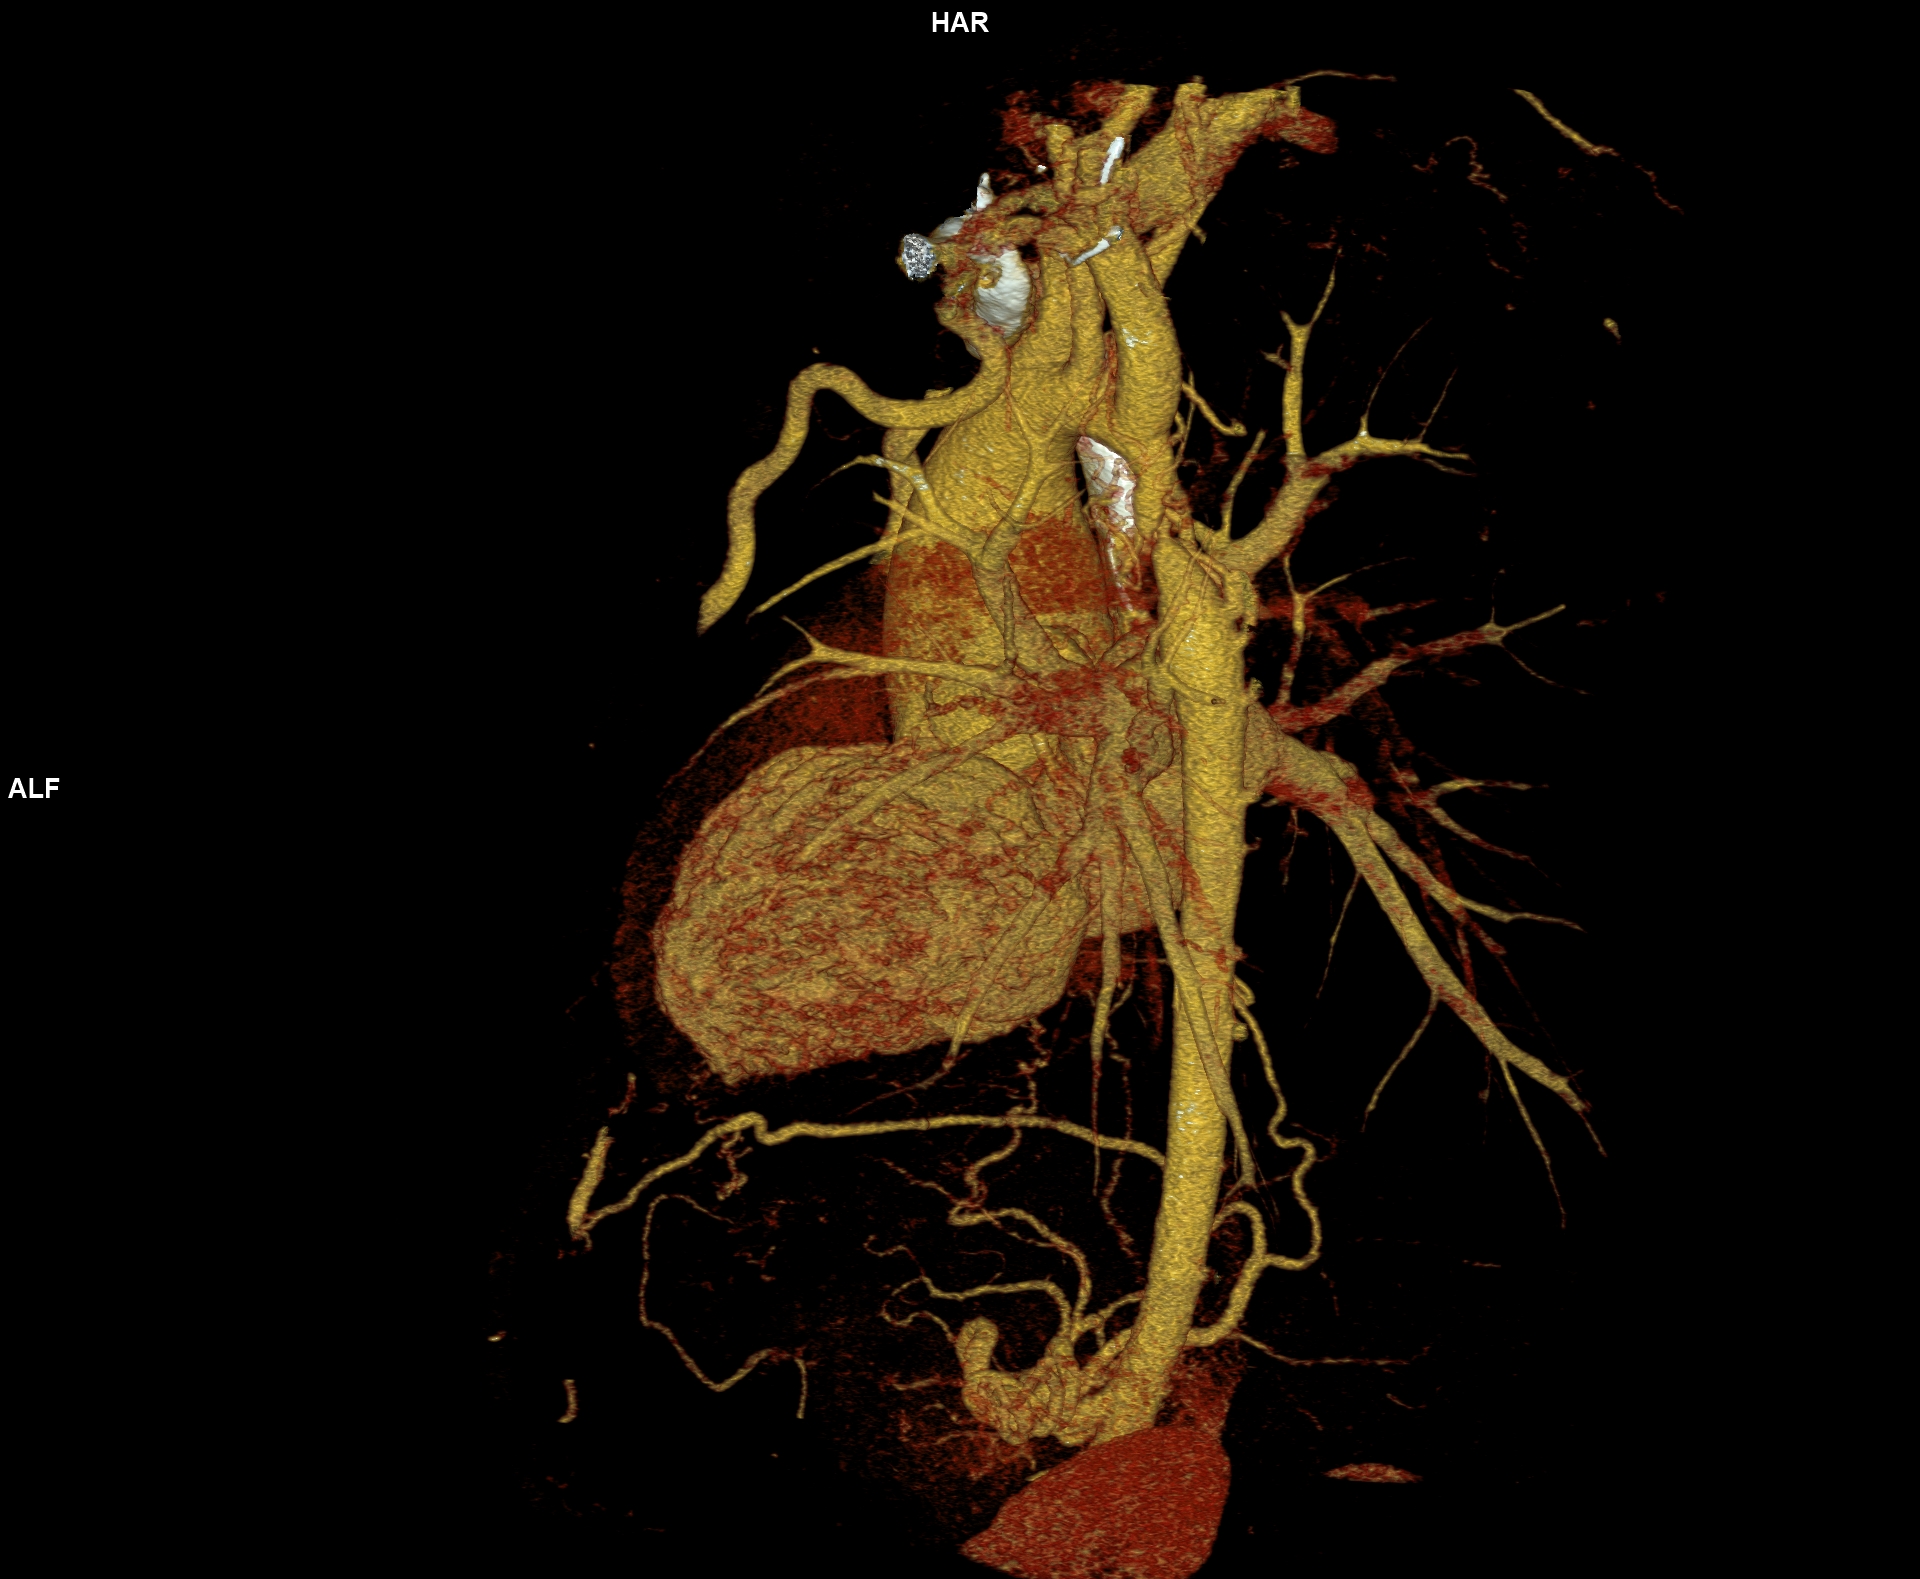

Figurile 6-10: reconstrucții volumice (VRT) din achiziție angioCT aorta toracică

Discuţie caz nr 109: Pacient cu suspiciune de coarctaţie de aortă – are indicație de angioCT aortă toracică; medicul radiolog la acești pacienți este indicat să efectueze investigația cu sincronizare ECG deoarece coarctaţia de aortă poate fi asociată și cu bicuspidie de valvă aortică, mai ales că la acest pacient ecografia cardiacă descria creștere de calibru a aortei ascendențe. Pe reconstrucția cine în planul valvei aortice din achiziția cardioCT cu sincronizare ECG se remarcă o valvă aortică morfologic tricuspidă, funcțional bicuspidă ce asociază ectazie de aortă ascendentă și coarctaţie de aortă descendentă cvasicompletă cu dezvoltare de circulație colaterală intercostală și mamară internă.